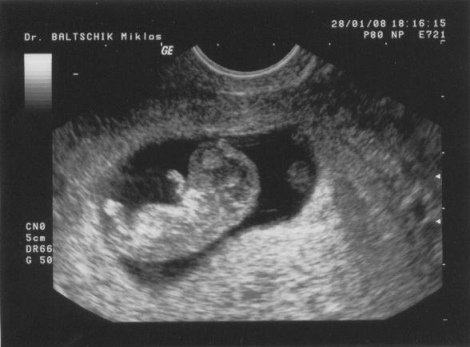

Z, az ülve nyolc centis, aki átjáróháznak használja a testemet, kezd az agyamra menni. Ő dönti el, mikor alszunk (mindig, leszámítva az este 7-10 közötti időszakot), ő dönti el, mit eszünk (nyers húst naranccsal), ő dönti el, megyünk-e buliba (nem), ő dönti el, mikor hányunk (ezt sajnos szinte soha nem tudja egyértelműen eldönteni, de folyamatosan fenntartja a lehetőséget), ő dönti el, melyik blogba írunk (ebbe). Az is a tudomásomra lett hozva, hogy nem fürödhetek forró vízben, különösen illatosított termékekkel, nem festhetek hajat, nem ehetem az általam kedvelt (és nem kedvelt) ételek 80%-át, nem mehetek elektromos eszközök közelébe, és úgy általában az lenne a legjobb, ha szülésig egy hintaszékben üldögélnék és az anyaság örömeiről merengenék, miközben felváltva kismamajógázom és beszélgetek a gyerekkel, mert különben (a) Z agykárosodott lesz (ha ezt a szőlő-kivi illatú tusfürdőm képes elérni nála, hát így járt), (b) elmegy a gyerek (ha csak a tizede igaz annak, amit állítanak, bio-abortuszklinikát fogok nyitni (vö. "otthonvetélés")).